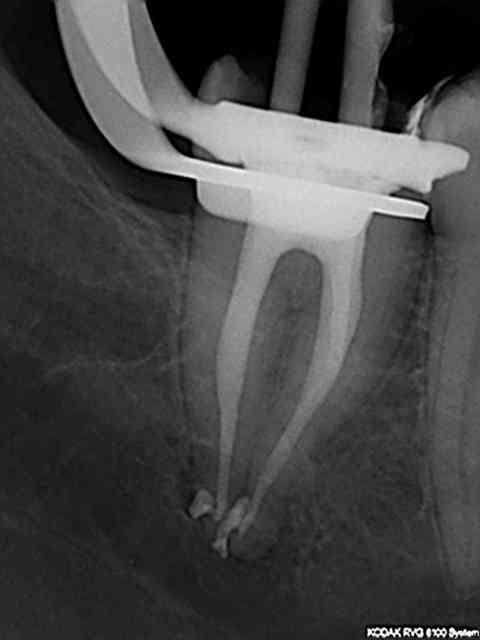

connais pas. Mais une de plus 30 mn, résultat reproductible à un train de sénateur, po pom, po pom.) Radio cone en place facultative mais bon des fois je coupe le bout du cone..